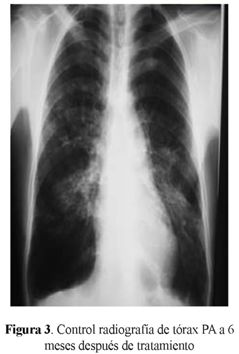

Evolución: al sexto mes de tratamiento control de inmunodifusión en gel Agar: negativo, fijación del complemento: reactiva 1:512, radiografía de tórax (figura 3)

Los criterios de cura son el mejoramiento micológico, clínico, radiológico, estabilización de inmunodifusión en doble gel de agar con resultados 1:2 o negativo (10).